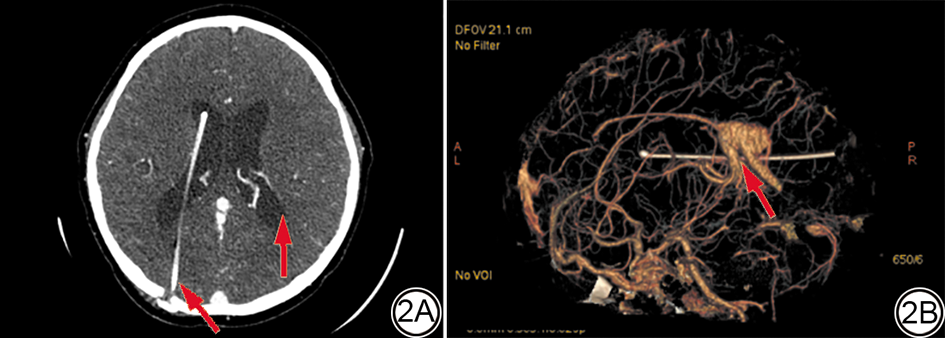

统计分析发现,不同类型的CVMs的检出情况在DSA、CTA、MRA及CTA联合MRA之间差异无统计学意义(χ2=4.626,P=0.969)。而与DSA(图1)相比,CTA、MRA单独检测检出CVMs的数量(34/38、33/38)低于DSA,差异具有统计学意义(P<0.05),而CTA与MRA联合诊断检出CVMs的数量(40/38)与DSA接近,差异无统计学意义(P>0.05)(表1)。典型病例的DSA图像、CTA图像和MRA图像分别见图1, 图2, 图3

图3  男,11岁,因脑出血入院,确诊为脑动静脉畸形。3A和3B:T1WI轴位及矢状位图像可见左侧脑室后角斑片状等信号(红箭),其内可见血管流空影;3C:MRA左侧胼周动脉可见畸形血管显影(红箭);3D:MRV左侧横窦增粗可见与胼周动脉间异常血管相连。MRA:磁共振血管成像;MRV:磁共振静脉成像。

Fig. 3  Male, 11 years old, admitted to the hospital due to cerebral hemorrhage and diagnosed with cerebral arteriovenous malformation. 3A and 3B: There are patchy signals in the posterior angle of the left lateral ventricle (red arrow), and vascular flow voids would be seen within it, in the T1W1 and sagittal images. 3C: Malformed vessels (red arrow) can be seen on the left peripons artery of the MRA scan. 3D: The left transverse sinus is thickened and connected with the abnormal vascular in the peri-capsular arteries on the MRV image. MRA: magnetic resonance angiography; MRV: magnetic resonance venography.